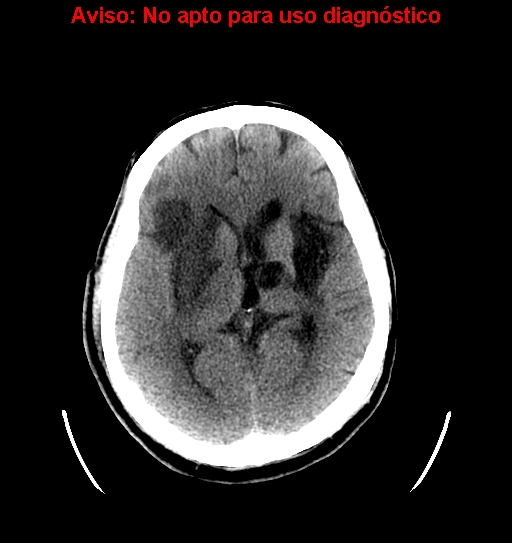

CASO 1:

Paciente con disminución de la conciencia y alteraciones de habla. El cuadro parece progresivo. Dislipemia y Diabetes Mellitus tipo II como antecedentes personales.

ASPECTS: Afectación Ribete Insular + Lenticular + Territorio M2 = 10 – 3 = 7 puntos.